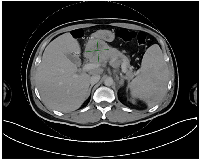

An abdominal ultrasound identified a lesion in the head of the pancreas. Further imaging with a contrast-enhanced computed tomography (CT) scan of the chest, abdomen, and pelvis confirmed a solid, heterogeneous mass in the pancreatic head, measuring 4.7 × 5.1 × 6.6 cm. Multiple prominent lymph nodes were observed in the retroperitoneal, gastrohepatic, para-aortic, and portocaval regions (Figure 1). Based on imaging and clinical presentation, pancreatic adenocarcinoma was initially suspected.

Figure 1

CT scan Abdomen axial view showing lesion within pancreas/adjacent peripancreatic lymphadenopathy.

Figure 1: CT scan Abdomen axial view showing lesion within pancreas/adjacent peripancreatic lymphadenopathy.